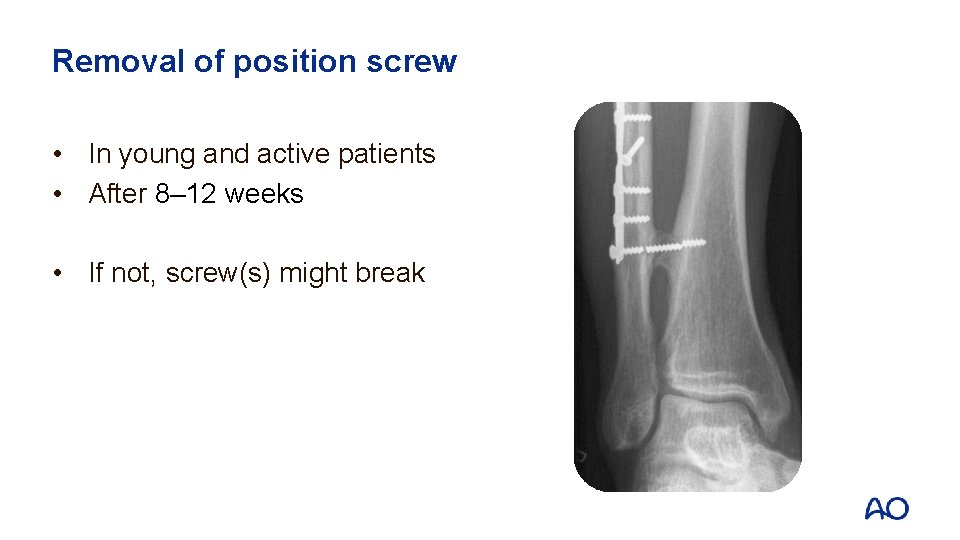

4. Syndesmosis―fixation • Position screw(s): one or two cortex screws 3. 5 mm

Removal of position screw • In young and active patients • After 8– 12 weeks • If not, screw(s) might break

After care • Back-slab for a few days until swelling reduced • Start early active joint motion exercises out of plaster slab • Cooperative patients are allowed immediate touch weight bearing • Remove sutures and do x-ray control after 2– 3 weeks • Remove position screws after 8– 12 weeks if bone healing is satisfactory